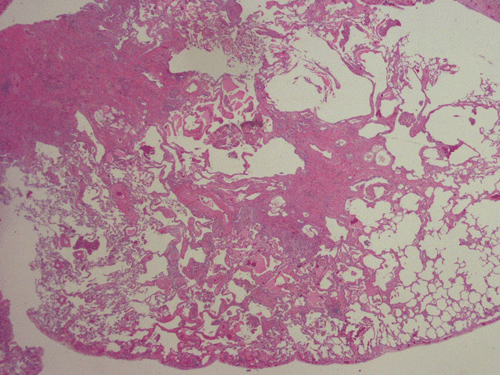

Clinical information: The patient was an asymptomatic, 60 year-old smoking male with a past history laryngeal cancer, status-post chemo- and radiation therapy. He was followed in the clinic for evidence of cancer recurrence. About one year ago, the patient was found to have a distinct coin lesion in the right upper lung lobe and multiple, small to minute, diffuse pulmonary nodules bilaterally. The base of the lung was relatively spared. Mediastinal lymphadenopathy was also demonstrated. A chest CT showed similar findings. An FNA was carried out for suspicion of malignancy on a pleural based nodule but the specimen has only non-diagnostic changes. The patient continued to be followed with chest CTs which demonstrated an increase in number of lung nodules, stable mediastinal lymphadenopathy and an interval development of interstitial fibrosis. He remained asymptomatic. A suspicion of infectious etiology was considered, although malignancy could not be ruled out. A tuberculin test was negative. A wedge biopsy obtained from the right upper lobe lung was performed. The followings are representative images of the biopsy material.

At scanning magnification (Panel A), the lung parenchyma is replaced by some coalescing fibrous nodules. The degree of involvement is variable at different fragments (Panel B and C). In the less affected areas, there are some fibrotic thickening of the septa (Panel C). In some areas, the changes are minimal and the pleural appear to be uninvolved (Panel D and E). In low to medium magnifications, these nodules of fibrosis contains a large number of hemosiderin laden macrophages (Panel F and G) admixed with fibrous tissue. The diagnostic tissue, however, is present in areas with increased cellularity. In these areas, there is a background of cells with a moderate amount of cytoplasm and bland nuclei. Some of these nuclei have kidney shape (arrow in Panel H). In some areas, many of the nuclei have a deep nuclear groove that resemble a coffee bean (arrow in Panel I). In the third type of areas, the nuclear grooving is not distinct (Panel J). Prominent eosinophilic infiltrations are almost always present. Immunohistochemistry on CD1a revealed many positive cells (Panel L). Also present in the specimen are multiple small blood vessels with thickened intima (Panel K). A Movat pentachrome stain demonstrates an internal elastic layer in these vessels and confirms that these are arteries (Panel M and N).